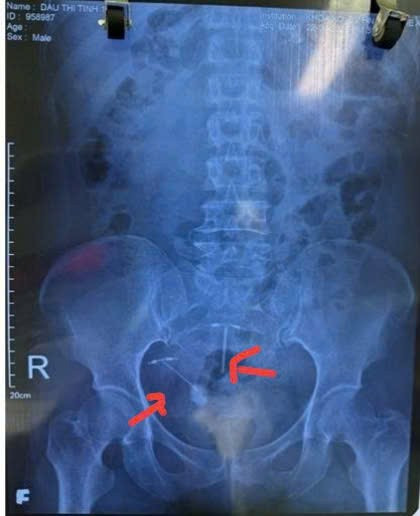

Hình ảnh phim X-quang trước mổ có 2 vòng tránh thai: Vòng bên trái dưới đâm vào bàng quang tạo sỏi, vòng bên phải trên đúng vị trí nằm trong buồng tử cung - Ảnh BVCC

Bệnh nhân được chuyển vào khoa Ngoại Tiết niệu, Bệnh viện Hữu nghị đa khoa Nghệ An làm đầy đủ các xét nghiệm như siêu âm, chụp X-quang, chụp cắt lớp vi tính ổ bụng… được chẩn đoán xác định vòng tránh thai lạc, xuyên thủng vào bàng quang và hình thành tạo sỏi trong bàng quang (kích thước viên sỏi 3×4 cm).